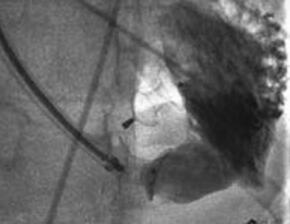

改进也针对复杂解剖的心尖部缺损,笔者称之为“逆向封堵”。虽然病例罕见但是有时会有伴有巨大心尖部壶腹需要较大封堵器方能完成的病例。有时候很值得怀疑这种病人是否能够局部封闭。存在一个缺损隧道,右室肌小梁部存在射流束。隧道方向与右房-右室轴线平行,垂直于右室前壁到缺损之间的轴线,因此根据笔者们的经验穿刺右室前壁通过经典方法穿过缺损极难(图10-48)。如果不改变导丝方向或者在心脏扭曲角度下穿刺前壁将无法通过此类缺损,而且该部位的肌小梁结构可能会不断缠绕导丝,此时由于输送系统是有弹性的,封堵也会受阻。如果遇到此类患者可以通过右房途径进行,切口可在右侧肋间进行。笔者利用一个更简单有效的方式进行。心脏上部拖出切口而不破坏TEE图像暴露室间沟(缺损壶腹部所在),延右室轴线直接穿刺进入通过缺损(图10-49)。而且隧道封堵的完成按照标准方式进行(图10-50)。在提供的病例中笔者选用了一个SQFDQ-Ⅰ14mm的封堵器,封闭了一个2岁患儿 的缺损。值得一提的是,笔者的病人没有任何并发症,没有左室出血危险。在笔者印象中患儿年龄也不比其他方法完成的患者年龄大。